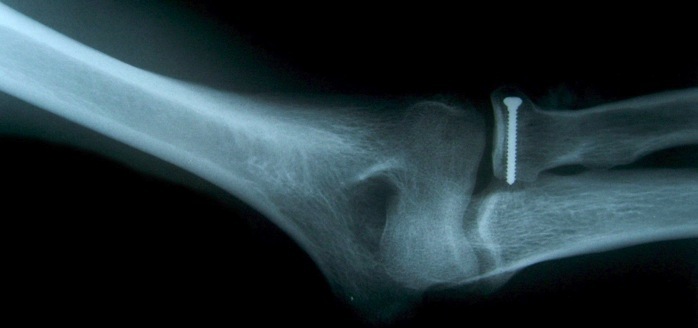

Analyse de radiographies

Analyse différentes radiographies. Essaye de reconnaître:

les différentes parties représentées: os, articulations,...

les malformations, les déplacements, les fractures.

l’âge des sujets: zones de croissances.